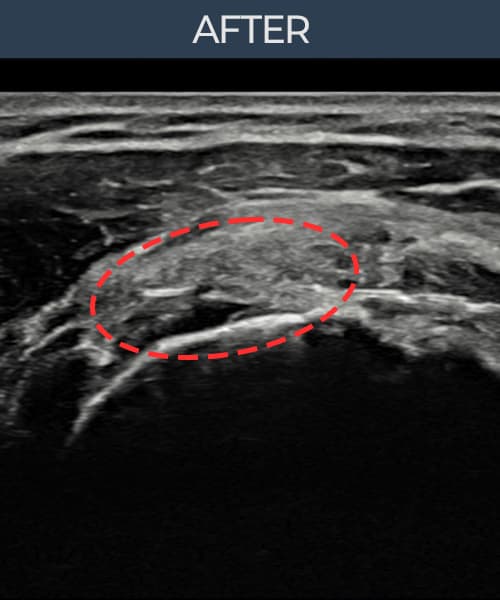

治療実績 — 超音波エビデンス

実際の患者様の施術前後の超音波画像。

手術なしで実現できる回復をご確認ください。

[経過期間: 23.07.18~23.09.14]

[縫縮術] 超音波検査にて左 棘上筋腱 광범위 部分断裂(15mm × 6mm (腱厚の約70%欠損))を確認。縫縮術施行後、腱の連続性が回復し、日常生活に復帰されました。